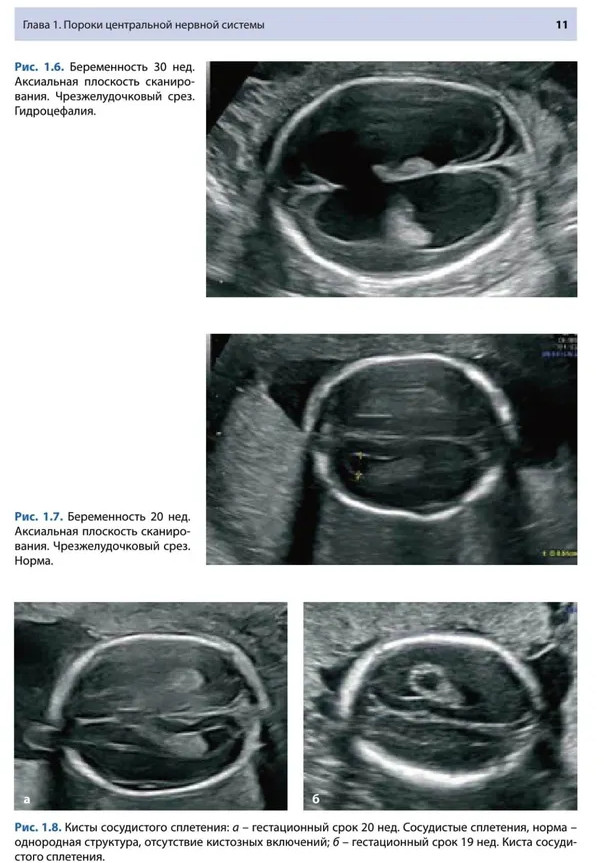

💳 Оплатить за товар можно при получении 🇰🇿 Есть бесплатная доставка по Казахстану от 1 дня 🎁 Копите бонусы с каждой покупки Одной из актуальных проблем современного акушерства является выявление пороков развития плода. Несмотря на активное развитие современных методов медицинской визуализации, каждый третий случай перинатальной смертности имеет различные варианты структурной или хромосомной патологии плода. Во многом это обусловлено субъективной интерпретацией получаемых ультразвуковых срезов, отсутствием единой методологии акушерского исследования. Данное учебное пособие посвящено вопросам стандартизации акушерского исследования в различные сроки гестации, представлены варианты нормы и патологии различных систем плода, предложена современная классификация пороков развития плода, алгоритм дифференциальной диагностики. Учебное пособие предназначено для практикующих специалистов ультразвуковой диагностики в области акушерства, пренатальной диагностики и акушеров-гинекологов. |